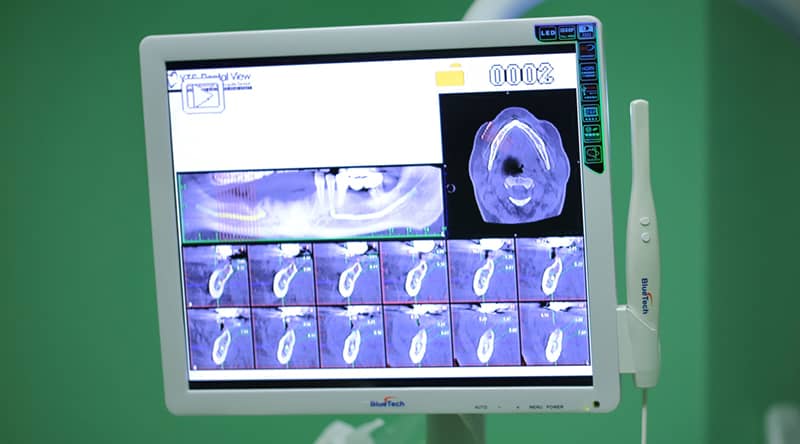

Câteva dintre cazurile noastre clinice cu imagini și explicații. Pacienți cu probleme funcționale sau estetice, genetice sau dobândite, unde s-au aplicat cu succes tratamente stomatologice personalizate.

Dacă aveți dinți lipsă, o soluție perfect potrivită și de durată este aceea cu implanturi dentare. Spre deosebire de alte restaurări dentare care ori sacrifică dinții vecini prin șlefuirea lor, ori folosesc baze din plastic sau acrilat ce acoperă gingia sau cerul gurii, implanturile dentare vor reface perfect dinții lipsă din zâmbetul tău.

Află mai multe pe pagina despre Implant Dentar.